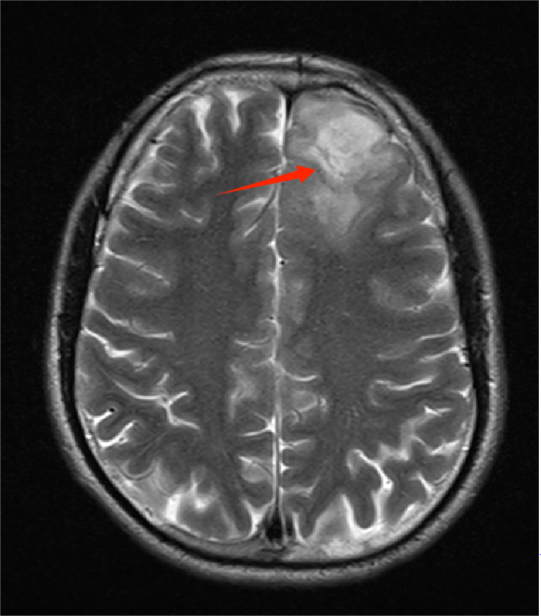

核磁共振結(jié)果:左側(cè)額葉團片狀異常信號影,考慮腫瘤性病變可能

醫(yī)生懷疑范先生左側(cè)大腦額葉存在占位性病變,考慮是腦腫瘤,建議盡快住院,進一步完善檢查和治療。就這樣,范先生住進了神經(jīng)醫(yī)學中心神經(jīng)外科二區(qū)。

醫(yī)生為其進一步完善增強核磁共振等檢查后,根據(jù)患者的影像檢查結(jié)果,初步懷疑是低級別腦膠質(zhì)瘤可能。治療團隊經(jīng)過充分術(shù)前評估及準備,為患者制定了個性化手術(shù)方案。